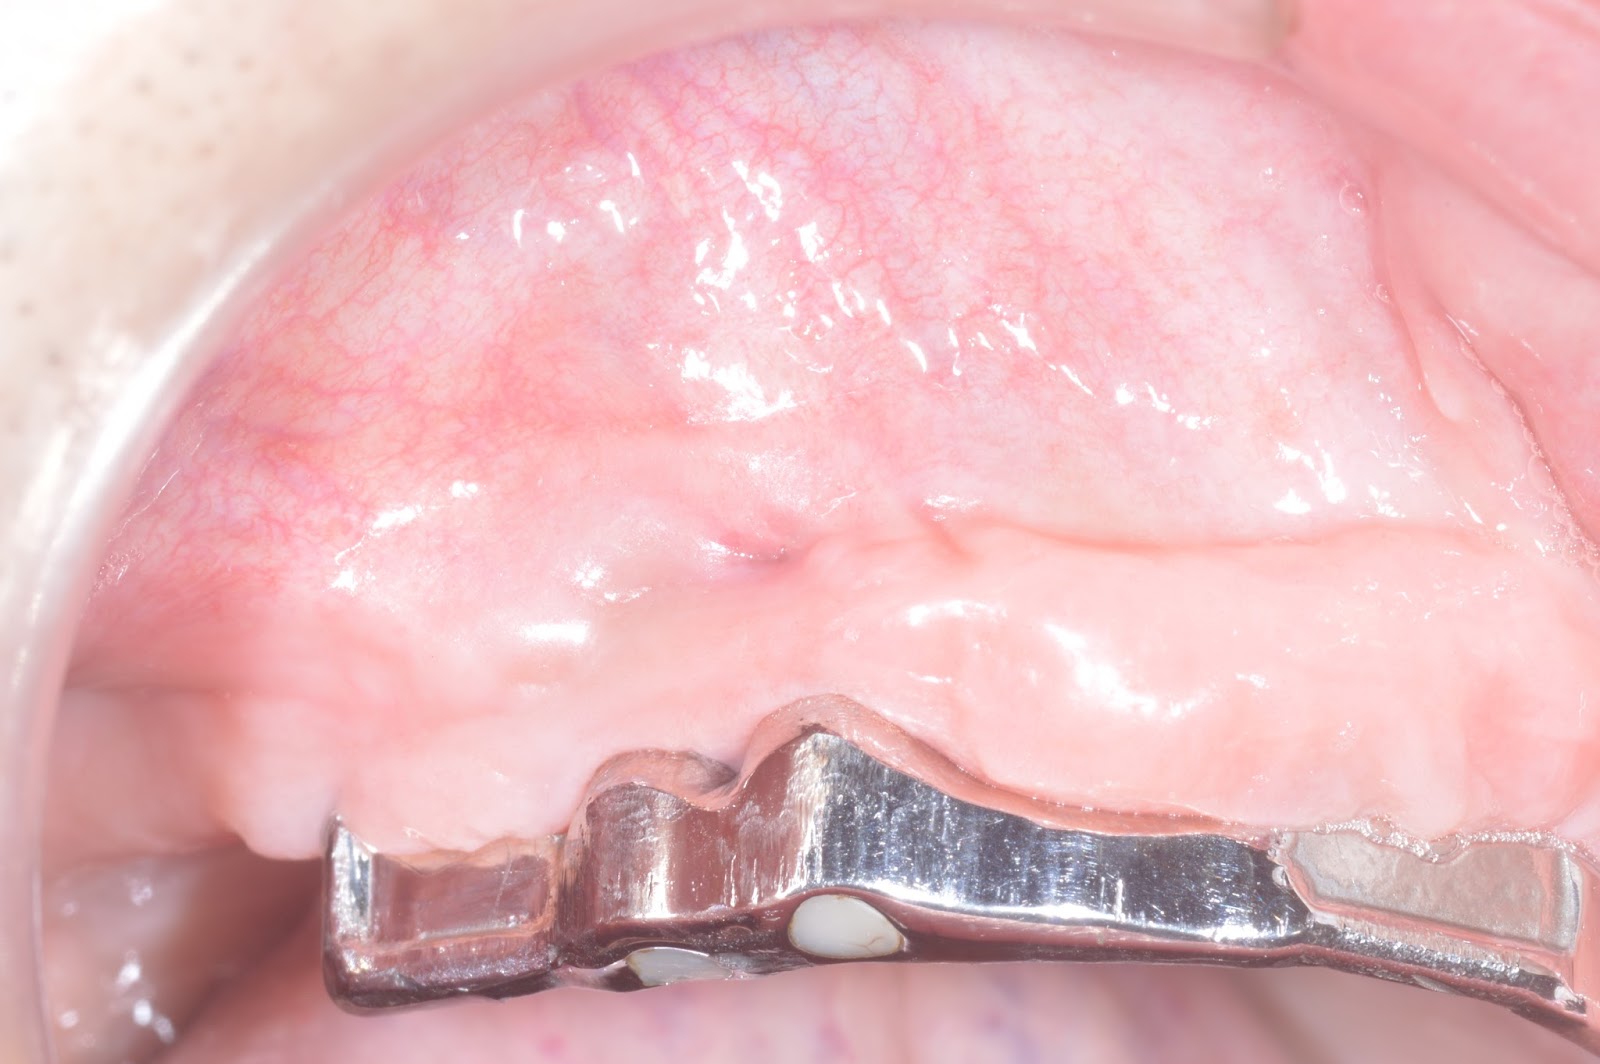

1 wk's healing

3 wks' healing

4 wks' healing

2 months' healing

6 Mo F/U